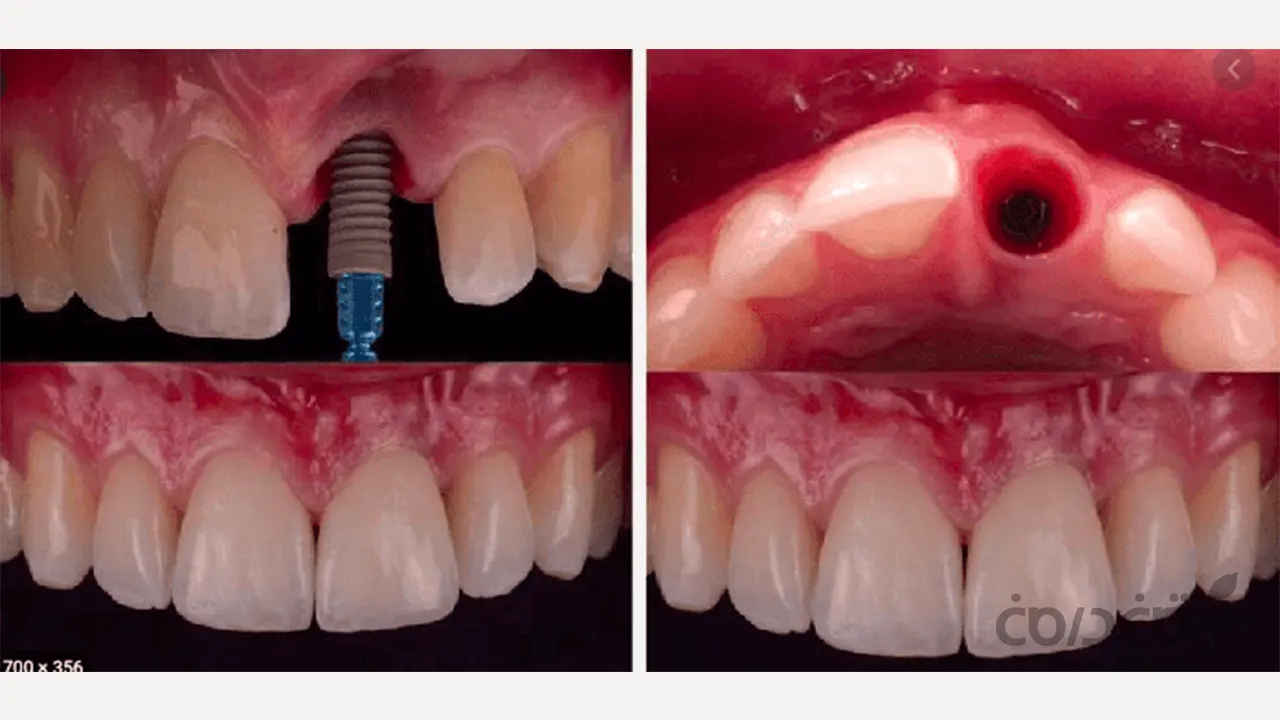

در مقایسه ایمپلنت با دندان واقعی، این مهم ترین شباهت عملکردی است. ایمپلنت دندان مستقیماً در استخوان فک کاشته شده و از طریق فرآیند یکپارچگی استخوانی (Osseointegration) به جزئی ثابت از بدن شما تبدیل می شود.

اتصال محکم به این معناست که ایمپلنت می تواند نیروهای شدید جویدن را دقیقاً مانند ریشه یک دندان سالم تحمل کند. شما می توانید بدون هیچ گونه نگرانی از لقی یا جابجایی، از خوردن استیک، آجیل، سیب و هر آنچه که دوست دارید، لذت ببرید. این ثبات کامل، وجه تمایز اصلی ایمپلنت با پروتزهای متحرک است.

اما واقعیت ایمپلنت دندان چیز دیگری است (یک اتصال مستقیم و بدون واسطه به استخوان)

در مقایسه ایمپلنت با دندان واقعی، باید بدانیم که ایمپلنت ها فاقد لیگامان پریودنتال هستند. ایمپلنت از طریق فرآیند اوسئواینتگریشن، به صورت مستقیم و کاملاً صلب به استخوان جوش می خورد. این اتصال، که به آن «آنکیلوز فانکشنال» می گویند، هیچ گونه انعطاف پذیری یا حرکت ریزی ندارد. این فقدان PDL، منجر به تفاوت های زیر می شود:

1. فقدان حسگر فشار

از آنجایی که هیچ عصب حسی بین ایمپلنت و استخوان وجود ندارد، شما حس لامسه دقیق دندان طبیعی را با ایمپلنت خود نخواهید داشت. شما می توانید فشار قوی را از طریق گیرنده های موجود در استخوان حس کنید، اما آن حس ظریف و دقیق از بین می رود.